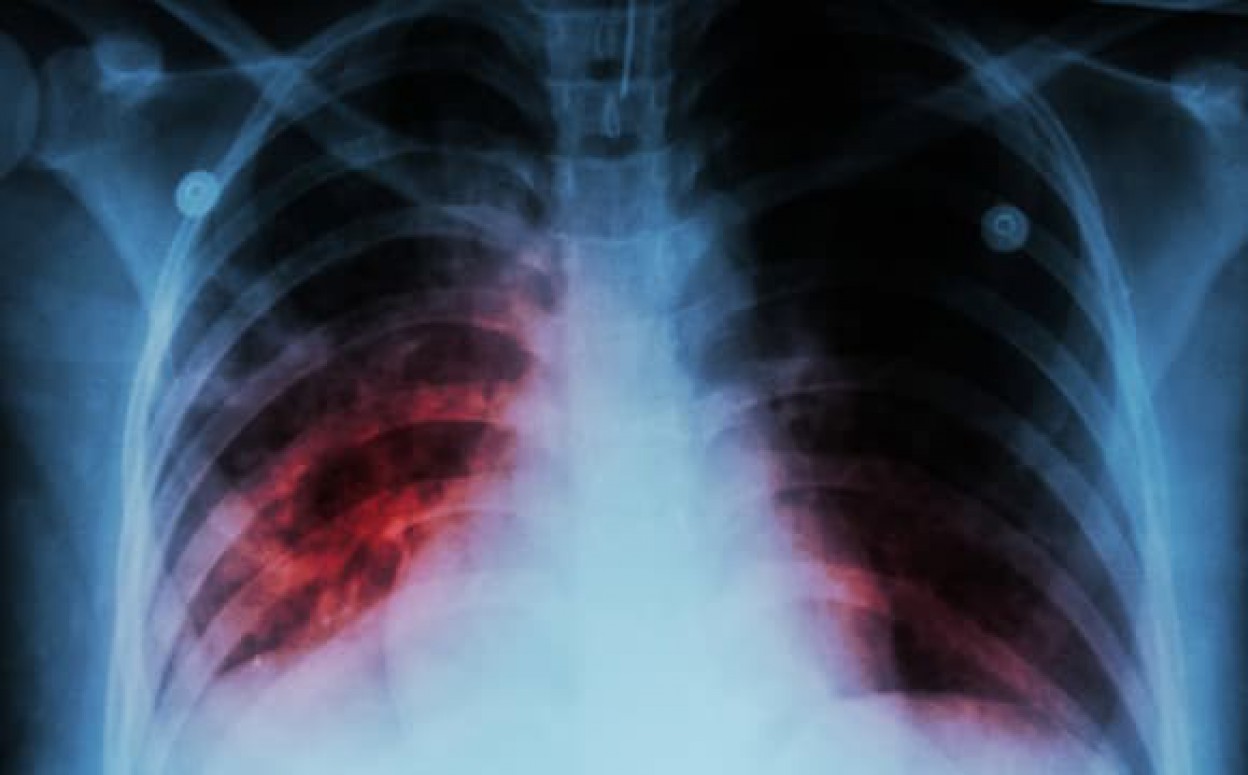

Nacionalinio visuomenės sveikatos centro Jonavos skyriaus specialistai informuoja, kad šiais metais Jonavoje užregistruota 20 naujai susirgusių atvira plaučių tuberkulioze atvejų. Visi susirgusieji yra suaugę asmenys, iš kurių 14 vyrų ir 6 moterys, gyvenantys kaime (10) ir mieste (10).

Pirmieji požymiai, kurie leidžia įtarti ligą, yra kosulys, silpnumas, prakaitavimas nakties metu, nesmarkus karščiavimas, kartais skausmas krūtinėje ar padidėję limfmazgiai. Jeigu kosulys nepraeina daugiau kaip per tris savaites, būtina pasikonsultuoti su gydytoju. Pasitikrinti ypač svarbu tiems, kurių šeimos nariai serga arba anksčiau sirgo tuberkulioze ar kurie turėjo sąlytį su sergančiu tuberkulioze asmeniu. Rizika užsikrėsti padidėja, jei bendraujama ilgai ir intensyviai su sergančiuoju atvira plaučių tuberkulioze, ypač prastai vėdinamose patalpose.

Ankstyvas ligos išaiškinimas ir gydymas yra pagrindinės priemonės, galinčios ne tik išgelbėti gyvybę, bet taip pat – užkirsti kelią infekcijos plitimui visuomenėje.